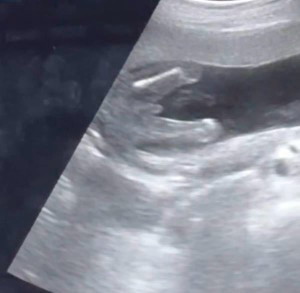

gender @ 17 weeks

hi mommies! ano po sa tingin nyo gender ni baby, boy po ba? and accurate na po kaya @ 17 weeks? thank you po sa sasagot 💗

boy po kapag po talaga boy madaling makta yan sa ultrasound hehe ako 15weeks palang kitang kita na lalake

boy po 🩵

ganyan po sa babies ko.. may nakalawit 😅 Boys po pareho

Yes it's a boy 🫶🏻🩵

boy, ganyan din saken. 18weeks nako

baby boy po 👶🏻congrats po